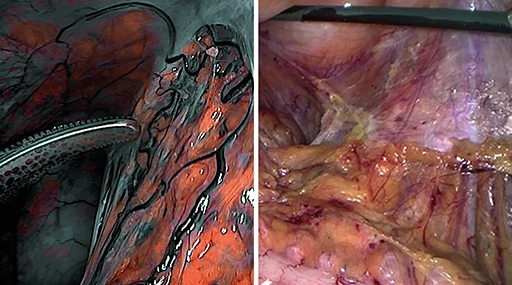

Miglioramento selettivo del colore (SCE)

Senza SCE

Le strutture e i vasi sono appena visibili.

Con SCE

Migliore visibilità delle strutture e delle imbarcazioni, aspetto naturale preservato.

Riduzione del fumo

Senza riduzione del fumo

Visibilità oscurata a causa della nebbia e del fumo.

Con riduzione del fumo

Migliore visibilità durante l’uso di strumenti HF/RF.